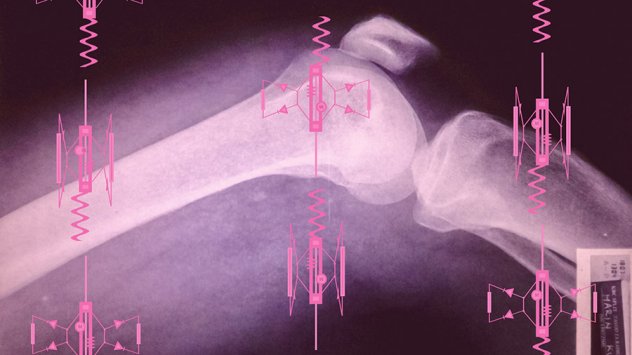

Tijelo bez organa umjetnička je koncepcija složena od četiri odvojena ali tematski povezana rada – Arhiva patoloških stakalaca, Kad narastem bit ću pacijent, 1966/ 1967/ 1994/ 2000, Kuzmić i Bez naziva (mehanizam). Nikolina Kuzmić u svom radu propituje pojmove biopolitike[1] i biotehnologije paralelno baveći se odnosom umjetnosti i medicinskih znanosti koji smatra sve očitijim i prominentnijim u današnjem vremenu.